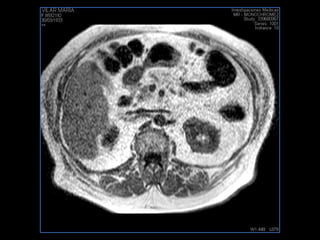

PROTOCOLO abdomen COR T2, AXIAL supresion grasa AX T1 +SAG T2  CON   GADOLINIO :  COR T1+AX T1(DIN) SAT: NO  FASE: RL THK: 6MM  COIL:  GAP: (FACTOR 1.4) 2MM FOV: 40 CM NEX:2 SINCRONIZACION RESPIRATORIA EN 3 O 4 CICLOS ALE

resonancia de abdomen